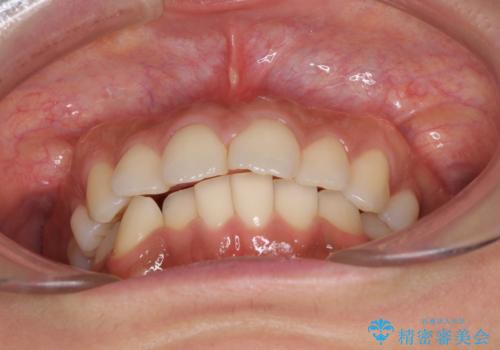

抜歯矯正の後戻り インビザラインによる再矯正治療

- 以前矯正治療をされていましたが、後戻りが起きたことを気にして来院された患者様です。

全顎的に認められた叢生を改善するため、インビザラインにて治療を行うこととしました。

前歯の叢生の改善を目的として、IPR(歯と歯の間を削る)と歯列全体の後方移動によって歯並びを整えることとしました。